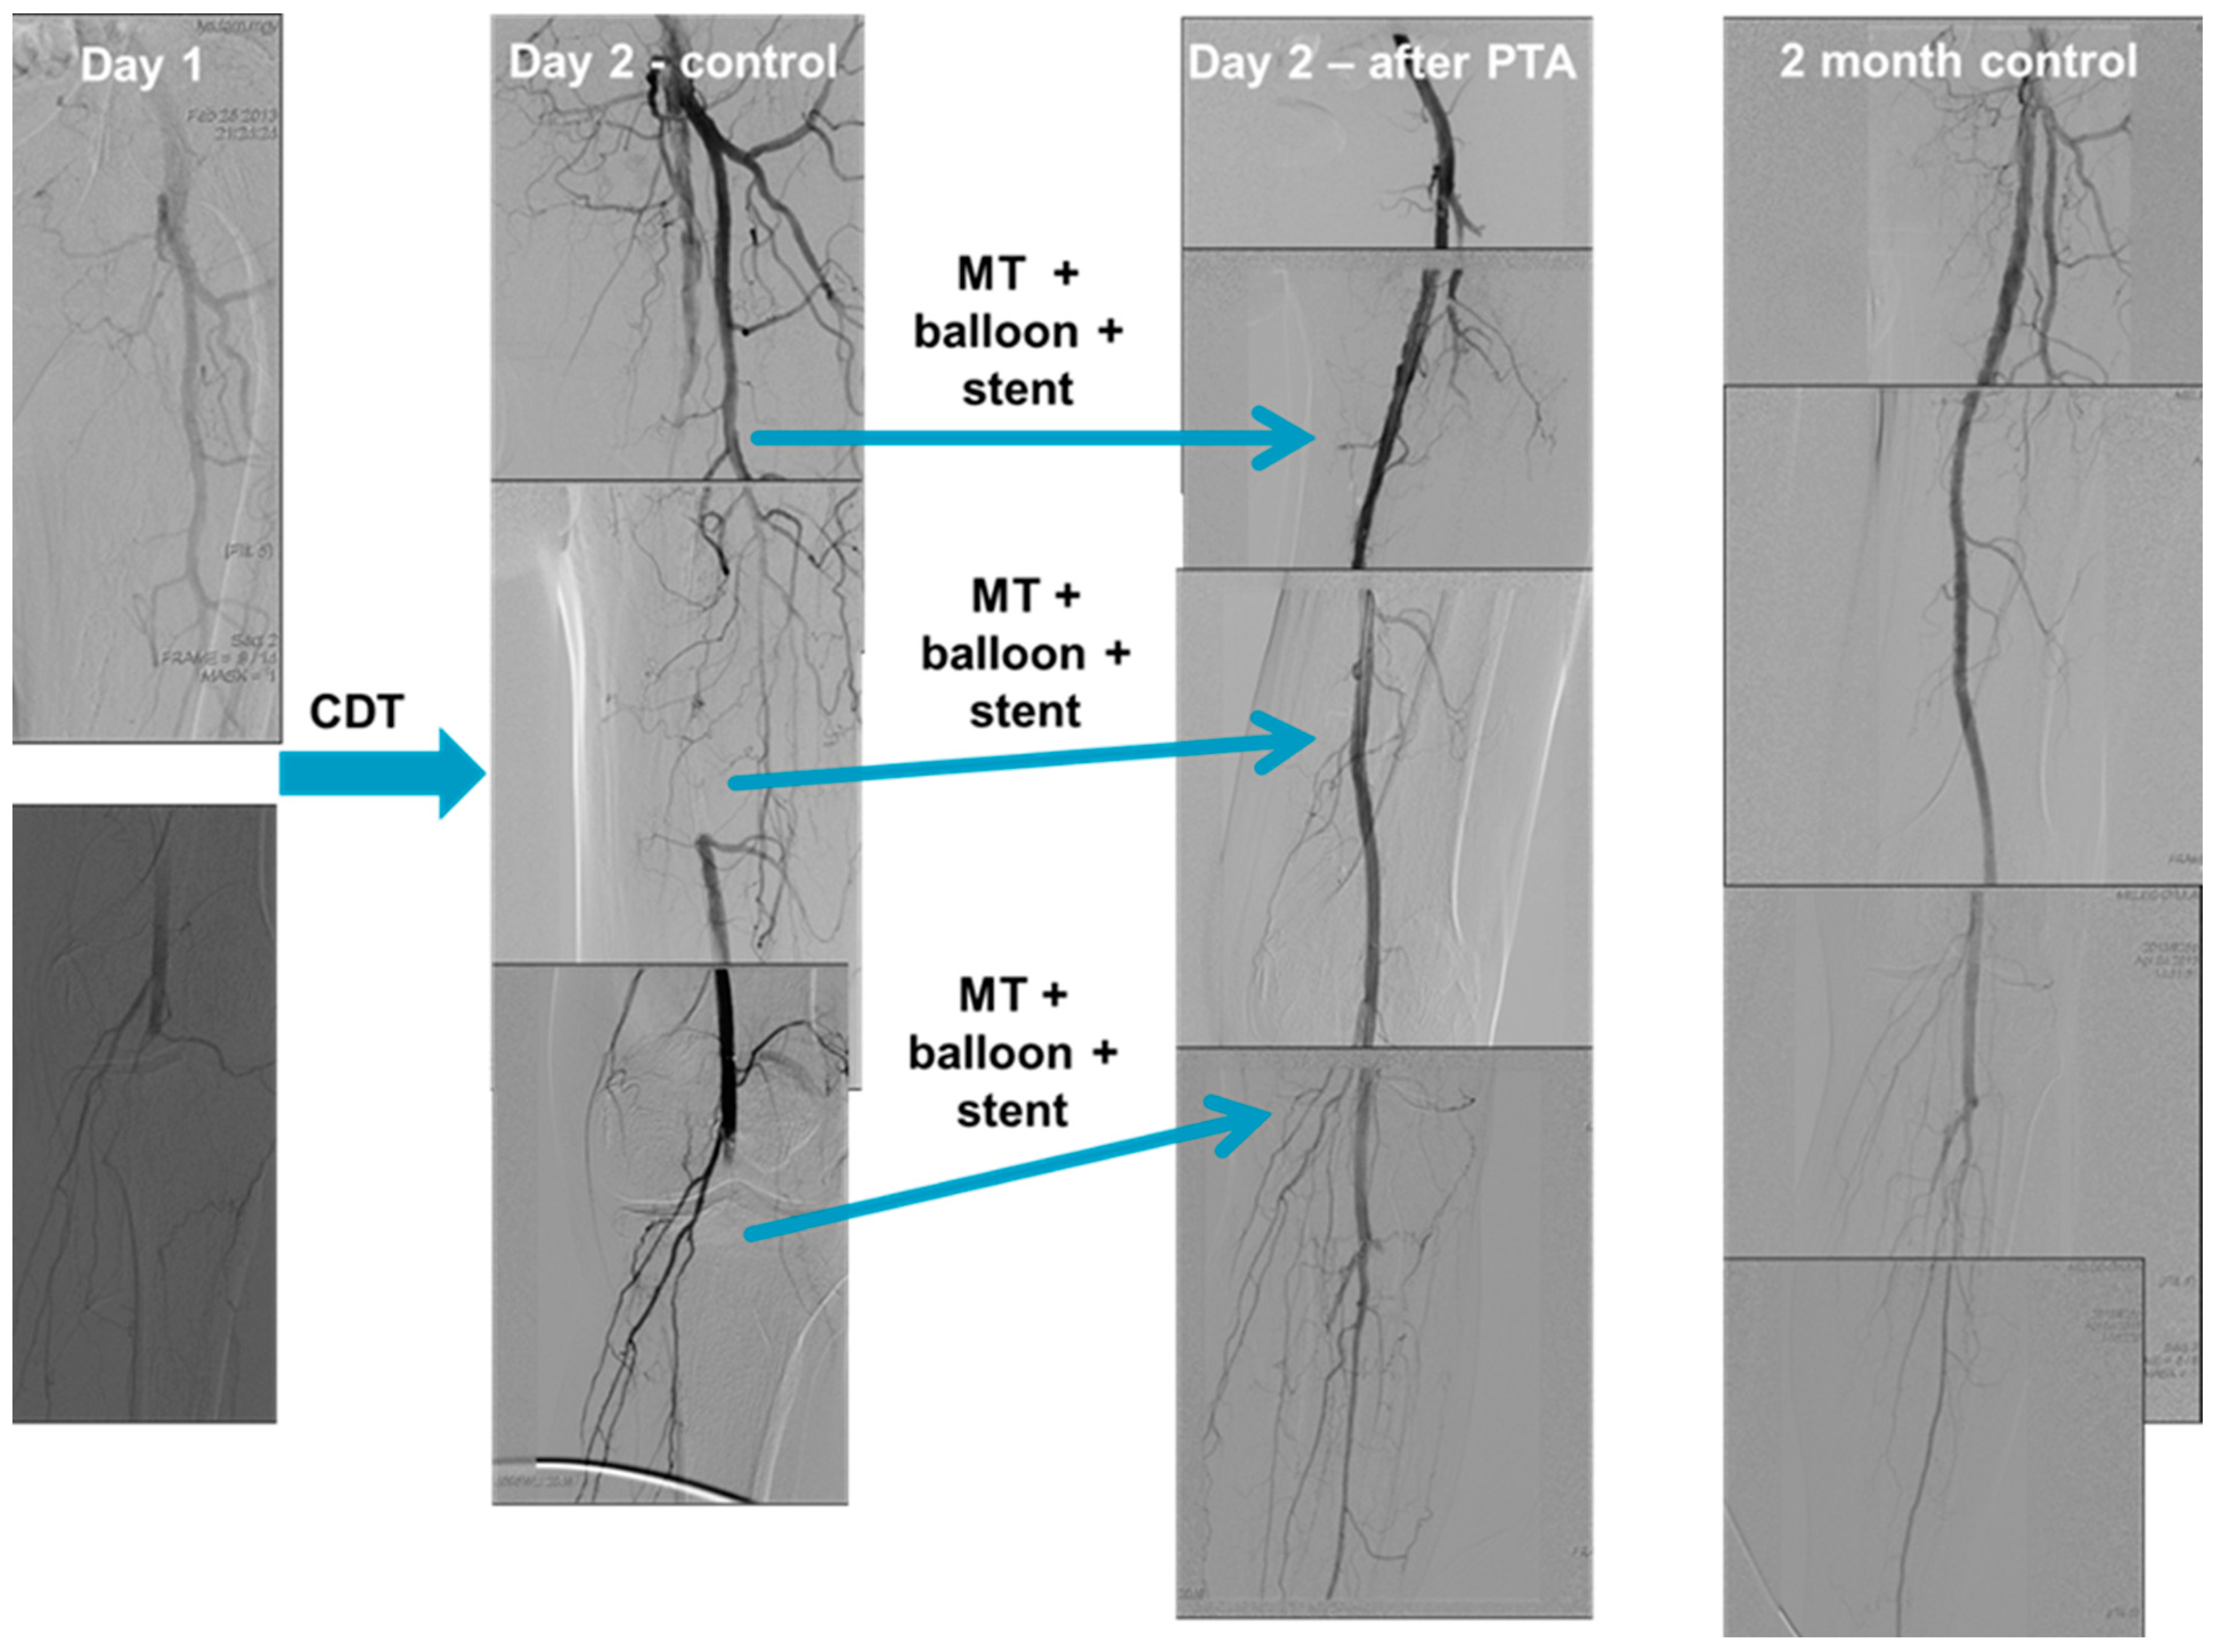

CDT was performed after selective angiography over a 5F pigtail catheter. The CDT was always initiated after a guidewire transversal test was conducted (the lesion was passed with a 0.18-inch guidewire) over a multiport thrombolytic catheter. If a CDT therapy was initiated, a control angiography was performed 24 h after local administration of a thrombolytic drug. If the thrombus continued to impede or completely block the flow despite the use of thrombolysis, additional thrombus aspiration was conducted. Similarly, if the lesion was significantly stenosed or dissected, additional balloon angioplasty or stent implantation was performed (Figure 1). The choice of treatment varied based on the location of the occlusion, the extent of clot formation, and the aetiology.

Figure 1. Catheter-directed thrombolysis (CDT) performed via access from a radial artery. Selective angiography performed using a radial approach (over a 5F pigtail catheter) shows a left common femoral artery occlusion without distal run-off. (Day 1) A guidewire transversal test, in which the lesion was passed with an 0.18-inch guidewire, was conducted over a multiport thrombolytic catheter. CDT was then initiated. On the first postoperative day, control angiography shows incomplete thrombus resolution and distal embolisation. (Day 2—control) Mechanical thrombectomy, additional balloon angioplasty, and stent implantation was performed in the left superficial femoral artery and in the left popliteal artery. Control angiography shows successful recanalisation with acceptable flow in the below the knee arteries. (Day 2—after PTA). Abbreviations: CDT—catheter-directed thrombolytic therapy; MT—mechanical thrombectomy; PTA—percutaneous transluminal angioplasty.